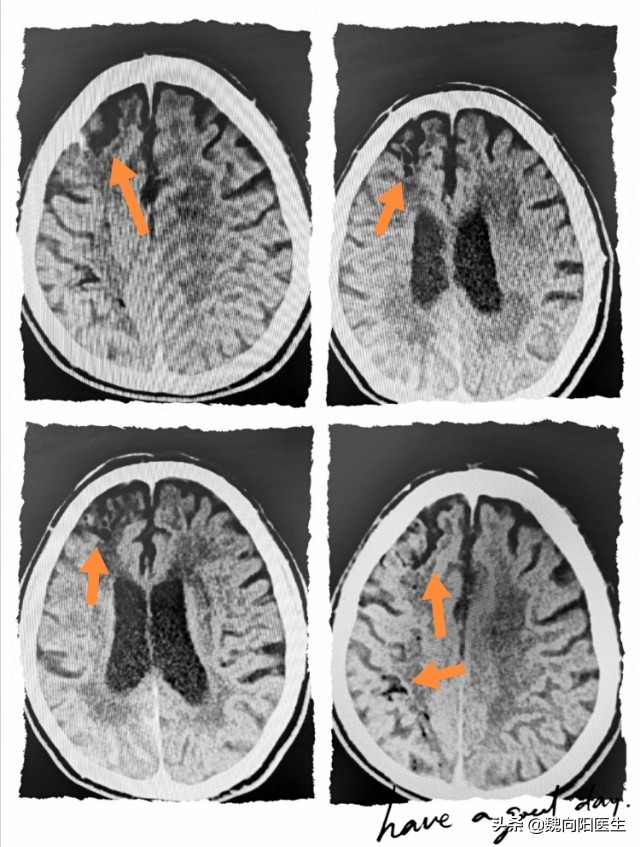

头CT提示:但是右侧 MCA 分布区可见大量散在、低密度病灶,推测为空气栓塞。

脑血管造影一般空气栓塞多见于脑部,一般空气经过动脉导管进入到颈动脉系统或椎动脉系统,进而导致颅内的脑血管血流淤滞;空气阻断了脑细胞与血液的接触,而出现脑细胞的缺血,严重者会出现脑梗死。